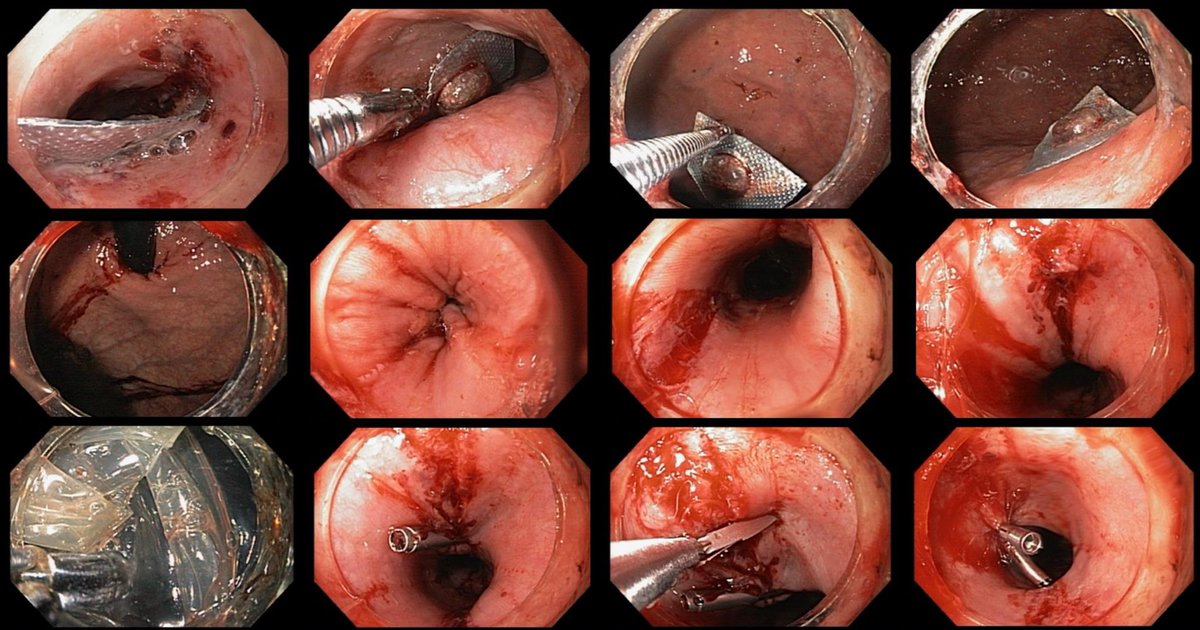

#MedCase 🧓 65 años con ingesta accidental de cuerpo extraño hace 24 horas. Intento fallido de extracción es referida para tratamiento. Endoscopia asistida por cap. Retiro con campaña “artesanal” de Hood. Se observa laceración esofágica y colocación de clips.

Sequence of first bite for a #Rose procedure for reparation of #bypass #RNY of 5 cm pouch with an anastomosis over 25 mm. We used the 33 mm @USGIMedical #Gprox avoiding the #APC due the lack of space #bariatricendoscopy @sa6ater @MetabolicEndo @SighPichamol thoughts?

2nd and 3rd bites. Less than 10 minutes procedure. Safe, clean and effective. @Clinica_Teknon #bariatricendoscopy #bypassreparation #ROSEprocedure #obesidad #endoscopia @EEndoscopia @TerapiasObesid